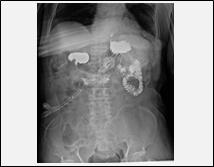

| 訪問レントゲン撮影により、次のような撮影が可能になります。 |

胃ろう交換の手技確認

胃ろう交換手技実施後、確認のための撮影が可能になります。

※在宅での胃ろう交換等が可能になります。

※胃ろう交換後の撮影にあたっては、造影剤を使用しますので事前にご相談ください。 |